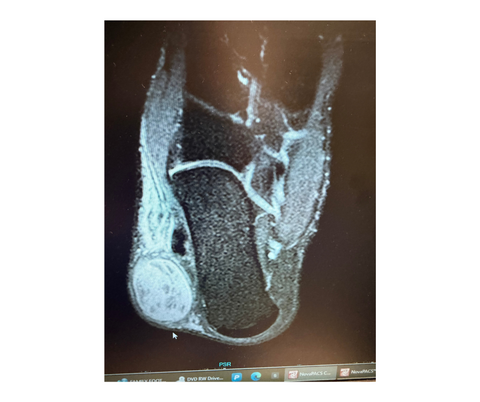

A plain film X-ray of the right foot revealed no significant findings. Subsequent magnetic resonance imaging (MRI) with and without contrast showed a 4.0 x 3.0 x 2.4 cm heterogenous enhancing mass. The MRI interpretation also noted multiple nonenhancing internal components to the mass, a few of which demonstrated an intrinsic hyperintense signal on T1-weighted images.